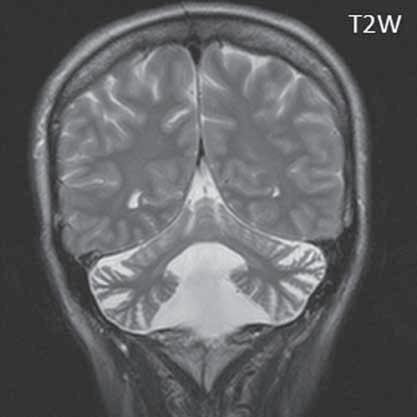

I.1.8 Dandy-Walkerova malformace (D-W variant, D-W komplex, D-W spektrum )

Zobrazení

D-W malformace je charakterizována hypoplazií vermis mozečku, rozšířením IV. mozkové komory, která se často cysticky vyklenuje dorzálně a může imitovat arachnoidální cystu, rozšířením zadní jámy lební a vysokým úponem tentoria s confluens sinum nad lambdovým švem. Okcipitální kost může být vlivem tlakových změn remodelována, existují i případy s porušením její kontinuity a encefalokélou. Hydrocefalus pozorujeme v 80 %, častá je přítomnost dysgeneze corpus callosum, schizencefalie.

D-W variant byl vyčleněn pro případy, kdy všechny základní příznaky nemusí být plně vyjádřeny nebo může některý zcela chybět. Bývá přítomna hypoplazie mozečku, což je dominantní příznak, IV. komora je obvykle rozšířena, někdy pozorujeme, že tvarem připomíná na axiální řezu „klíčovou dírku“, zadní jáma lební naopak rozšířena nebývá.

Obr. I.1.8e Dandy-Walkerovo spektrum (hypoplazie vermis, IV komora je rozšířená a široce zeje) (snímky zapůjčeny z archivu as MUDr J Lisého, CSc )

Obr. I.1.8f Dandy-Walkerovo spektrum (hypoplazie vermis, IV komora je rozšířená a široce zeje) (snímky zapůjčeny z archivu as MUDr J Lisého, CSc ); stejný pacient jako na obr I 1 8e

Obr. I.1.8g Dandy-Walkerovo spektrum (hypoplazie vermis, IV komora je rozšířená a široce zeje), (snímky zapůjčeny z archivu as MUDr J Lisého, CSc ); stejný pacient jako na obr I 1 8e, f